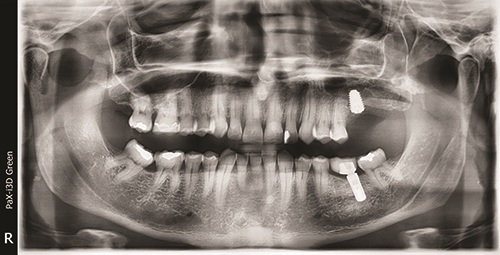

This case involved a 45-year-old male who lost tooth #14 because of periodontal disease, and after extraction, lost bone support to place an implant in the site. The patient had no provisional appliance but was ready for a permanent solution to the missing first molar. The patient had a thick biotype; hard and soft tissues were within normal limits, with no popping or clicking of the temporomandibular joint and no pain from the muscles of mastication. Maximum opening was 40 mm. A CBCT was taken to determine any anatomical structures of concern, if any buttress was present that would make the sinus lift more difficult, and if any anatomical structures were present in the lateral wall of the sinus (the anterior branch of the superior anterior artery PSA). On evaluation, it was found that the height was inadequate at 1.4 mm, the width was adequate at 8 mm, and the depth was also inadequate (Figs. 1 and 2). Thus, implant placement would be compromised. The use of osseodensification drills was contraindicated, as there was inadequate bone to perform a vertical sinus lift without tearing the sinus membrane, with an elevation of 7–10 mm. Thus, a lateral sinus wall approach was indicated to gain sufficient height for placement of an implant at least 10 mm in length.

Fig. 2

The CBCT was sent to a maxillofacial radiologist for evaluation to determine whether any pathology had been missed by this author.